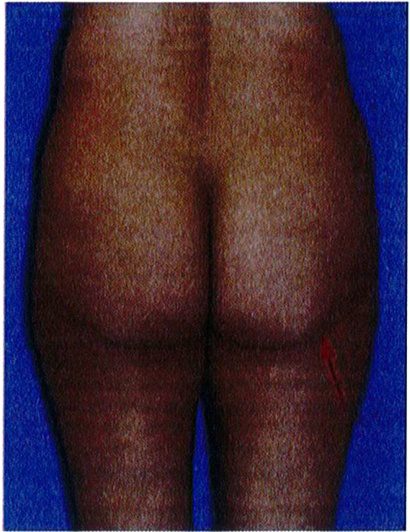

Hình 1. (A) Hình thể toàn bộ vùng mông phụ thuộc vào khung xương, cơ mông lớn, vị trí và lượng mỡ dưới da, độ căng của da. (B) Khung mông, với cơ môna lớn đã được tách ra.

Over rall Buttock Shape : Hình thể toàn bộ vùng mông Gluteal muscle: Cơ mông Gluateal muscle(gluteal shape): Hình dạng cơ mông Frame: Khung